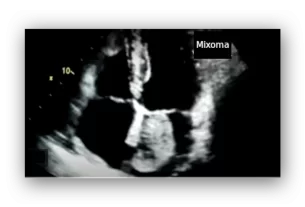

A cardiac ultrasound (echocardiogram) can confirm that the heart structure is normal. If no abnormalities are found, no further tests are needed.